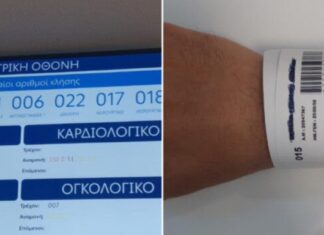

Ψηφιακό «βραχιολάκι» στα ΤΕΠ: Τα καλύτερα και τα χειρότερα νοσοκομεία στις επιδόσεις της αναμονής...

Το «βραχιολάκι» μπήκε στη ζωή των ασθενών...